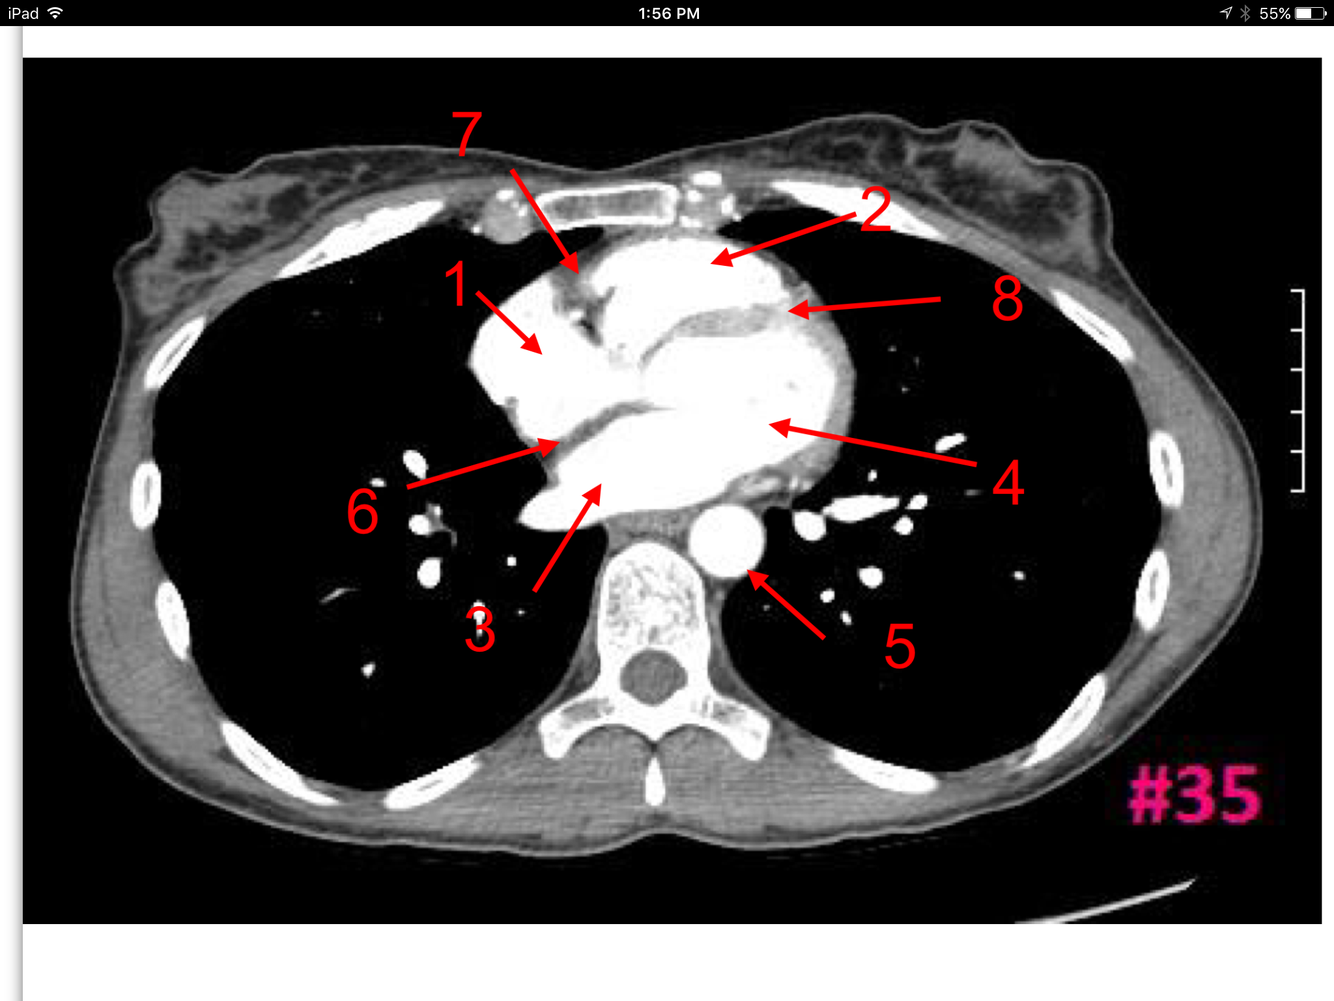

21

Q

Study These Flashcards

A

Rt atrium

Rt ventricle

Lt ventricle

Thoracic aorta

Interatrial septum

Rt atrioventricular septum

Interventricular septum